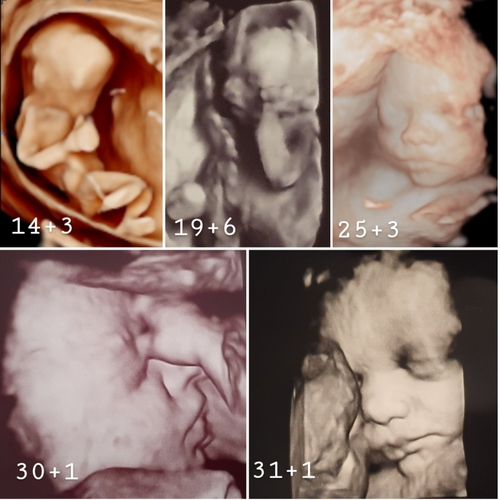

De aan te raden periode voor een 34D pretecho is tussen de 25 en 30 weken. Adjust machine settings follow the rules as for 2D for the best 3D resolution. Echo op 5 weken.

Mocht de baby helaas niet goed liggen voor 3D beeld dan mag je zonder extra kosten nog een keertje terugkomen. 3D echo 25 weken. 3D echo 30 weken.

Kan gedurende de hele zwangerschap beste te doen tussen de 24-30 weken. 3D echo 30 weken. Powered by Create your own unique website with customizable templates.

De ruimte geeft de pretecho meer kans van slagen omdat er genoeg vruchtwater tussen uw kindje en de baarmoederwand in moet zitten om het goed. Lieve mensen na 4 jaar gaat SOON pretecho stoppen. -- Houd er rekening mee dat een 3D4D echo tot 30 weken meestal goed lukt.